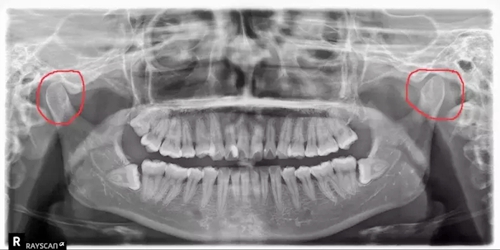

牙科醫(yī)生在看患者的X光片的時候,經(jīng)常能看出來有的人有偏側(cè)咀嚼的習慣,導致關(guān)節(jié)一側(cè)大一側(cè)小。

(如下圖:)